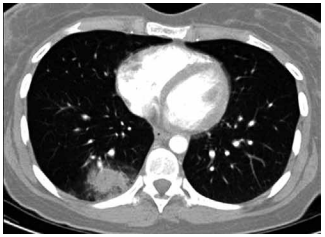

Mulher de 31 anos, recentemente diagnosticada com

leucemia mieloide aguda, é internada com neutropenia

febril doze dias após o primeiro ciclo de quimioterapia de

consolidação com citarabina em altas doses. Ela é tratada adequadamente com cefepima intravenosa. Sete

dias após, as hemoculturas são negativas e a contagem

de leucócitos está começando a se recuperar. Ela agora

apresenta febre de 38 °C, tosse e desconforto torácico

pleurítico. Os níveis séricos de galactomanana e beta-glucana estão elevados. A tomografia de tórax realizada

agora é mostrada a seguir: